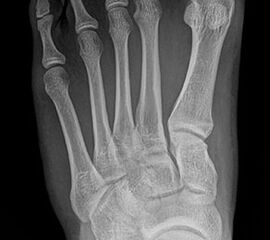

Bei einem juvenilen Hallux valgus handelt es sich um eine schon im Kindes – oder Adoleszentenalter 1 bestehende Valgusdeviation der großen Zehe bei Spreizfuß mit vergrößertem Intermetatarsalwinkel I / II aufgrund einer Adductionsstelllung des Metatarsale I – Metatarsaus primus varus.

Im Gegensatz zum Hallux valgus des Erwachsenen ist die Valgusabweichung der großen Zehe meist geringer ausgeprägt als bei Erwachsenen, der Intermetatarsalwinkel oft stark vergrößert. Die Angaben ab wann der Intermetatarsalwinkel als vergrößert gilt schwanken zwischen > 9° 2 und >14°3. Das Ausmaß der Beschwerden korrelieren nicht mit dem Auftreten und dem Schweregrad der Deformität (Zollinger 1990, Zollinger 1993). Begünstigend wirkt eine Schrägstellung des ersten Tarsometatasalgelenkes (Hefti 1998) und eine Hypermobilität dieses Gelenkes 2 in Kombination mit einer Bindegewebsschwäche. Häufig liegt eine positive Familienanamnese vor. In einer Untersuchung von Coughlin fand sich eine Vererbung über die mütterliche Linie in 72%, ein milder bis stark ausgeprägter Knick-Senkfuß in 17% (das entspricht der Quote von Knick-Senkfüßen in der Normalbevöl­kerung) aber in 22% ein Pes adductus, das ist wesentlich mehr als in der Normalbevölkerung zu erwarten wäre 4. Auch für Hefti (1998) gilt der Pes adductus als Komponente des Sichelfußes als begünstigend. Zur Inzidenz des Hallux valgus juvenilis finden sich je nach Autor verschiedene Angaben. Nach Auswertung von Schuluntersuchungen liegt die Häufigkeit zwischen 1,6 % bis 17% 56. Häufig tritt die Fehlstellung doppelseitig auf. Der Anteil der betroffenen Mädchen liegt 4-5x höher als bei Jungen (Lamprecht 2015).

Standard ist die belastete Röntgenaufnahme des Fußes dorso-plantar und seitlich. Günstig ist eine Röhrenkippung von 10°-20°, um die Gelenke der Lisfranc-Linie einsehen zu können.

Ergänzend kann eine Schrägaufnahme hilfreich sein. Bei Metatarsalgien oder Pathologien der Sesambeine liefert die Sprinteraufnahme zusätzliche Informationen. Bei einer Pes planovalgus Fehlstellung wird ergänzend ein Saltzman view durchgeführt.